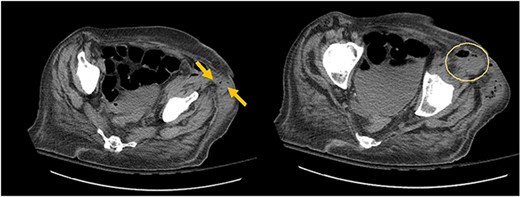

The patient had leukocytosis of 18.23 (Normal: 3.4–11 k/cmm) and CT scan of the abdomen pelvis without Intravenous contrast showed sigmoid diverticulitis with partial resolution of psoas abscess. However, it revealed a tract from the abscess to the hip (Image 3). After a prolonged discussion with the patient, she agreed to proceed with surgical intervention. She underwent exploratory laparotomy. There was a firm, inflamed sigmoid colon densely adherent to the psoas muscle. She also had two loops of small bowel that were densely adhered to the colon. Those loops were removed in block and two small bowel anastomoses were created. After mobilization of the sigmoid colon, there was a defect with fistulization to the psoas muscle. There was a significant amount of purulent fluid coming out of the psoas muscle, which was copiously suctioned and irrigated. Then, an end colostomy was created. A 3 cm elliptical incision was made in the left thigh and the skin was removed. The tissue was probed digitally, and we were able to identify the tract with a significant amount of stool and purulent fluid emanating from the left thigh. Once the cavity was entered, pressure was applied on the thigh, the psoas abscess was draining as well, indicating communication. We drained as much as we possibly could through both the psoas and the left thigh abscess and irrigated them copiously and packed. The patient was hemodynamically stable during the procedure and was extubated and transferred to the floor. The nasogastric tube was removed on post operative day 2, and she started on a diet. Her left hip dressing was changed daily with no signs of further infection. She continued on antibiotics during all hospital stay. She was discharged to Nursing home for physical therapy and adequate wound care. Specimen pathology was negative for malignancy. Patient was successfully reversed 6 months later.

Arrows shows extension of psoas abscess through abdominal wall in the surrounding tissues around the hip. There is not Hip bone involvement. Circle shows abscess next to the hip.